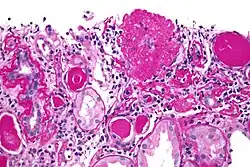

| Light micrograph of focal segmental glomerulosclerosis, hilar variant. Kidney biopsy. PAS stain. | |

On histology, FSGS manifests as scarring (sclerosis) to segments of glomeruli; moreover, only a portion of glomeruli are affected.[7][20][21] The focal and segmental nature of disease seen on histology help to distinguish FSGS from other types of glomerular sclerosis.[21]

Diagnosis of FSGS is made by renal biopsy that includes at least fifteen serial cuts with at least eight glomeruli.[32][33] Histologic features include sclerosis (scarring) of a portion (average: 15%) of the glomerular space, with only a portion of glomeruli manifesting any sclerosis.[33]

Five mutually exclusive variants of focal segmental glomerulosclerosis may be distinguished by the pathologic findings seen on renal biopsy:[35]

- Collapsing variant

- Glomerular tip lesion variant

- Cellular variant

- Perihilar variant

- Not otherwise specified (NOS) variant

Recognition of these variants may have prognostic value in individuals with primary focal segmental glomerulosclerosis. The collapsing variant is associated with higher rate of progression to end-stage renal disease, whereas the glomerular tip lesion variant has a low rate of progression to end-stage renal disease in most patients.[9] The cellular variant shows similar clinical presentation to collapsing and glomerular tip variant but has intermediate outcomes between the other two variants.[9]